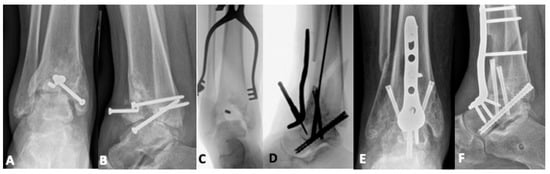

5.2. Joint-Sacrificing Reconstruction

5.2.2. Tibiotalar Arthrodesis